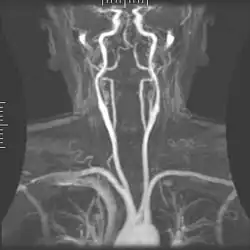

Magnetic resonance angiography

Magnetic resonance angiography (MRA) generates pictures of the arteries to evaluate them for stenosis (abnormal narrowing) or aneurysms (vessel wall dilatations, at risk of rupture). MRA is often used to evaluate the arteries of the neck and brain, the thoracic and abdominal aorta, the renal arteries, and the legs (called a "run-off"). A variety of techniques can be used to generate the pictures, such as administration of a paramagnetic contrast agent (gadolinium) or using a technique known as "flow-related enhancement" (e.g., 2D and 3D time-of-flight sequences), where most of the signal on an image is due to blood that recently moved into that plane (see also FLASH MRI).[53]

Techniques involving phase accumulation (known as phase contrast angiography) can also be used to generate flow velocity maps easily and accurately. Magnetic resonance venography (MRV) is a similar procedure that is used to image veins. In this method, the tissue is now excited inferiorly, while the signal is gathered in the plane immediately superior to the excitation plane—thus imaging the venous blood that recently moved from the excited plane.[54]